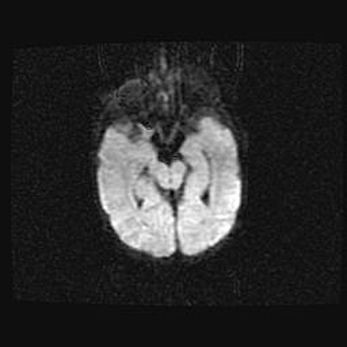

Подострая гематома правой гемисферы мозжечка.

Наружная гидроцефалия.

Возраст: 15 дней

Вес: 3100 г

Пол: женский

Окружность головы: 37 см

Срок гестации: 35-36 недель

При открытой наружной форме гидроцефалии у новорожденных расширяются и переполняются субарахноидные пространства.

Кровоизлияния в мозжечок имеют две клинико-анатомические формы: полушарные гематомы и кровоизлияния в червь.

К появлению этой патологии может привести: повреждения головного мозга, возникающие в результате асфиксии и гипоксии плода при беременности, или травмы во время родов. Редко гематома мозжечка может быть результатом первичной коагулопатии и сосудистой мальформации, диссеминированном внутрисосудистом свертывании, изоиммунной тромбоцитопении.